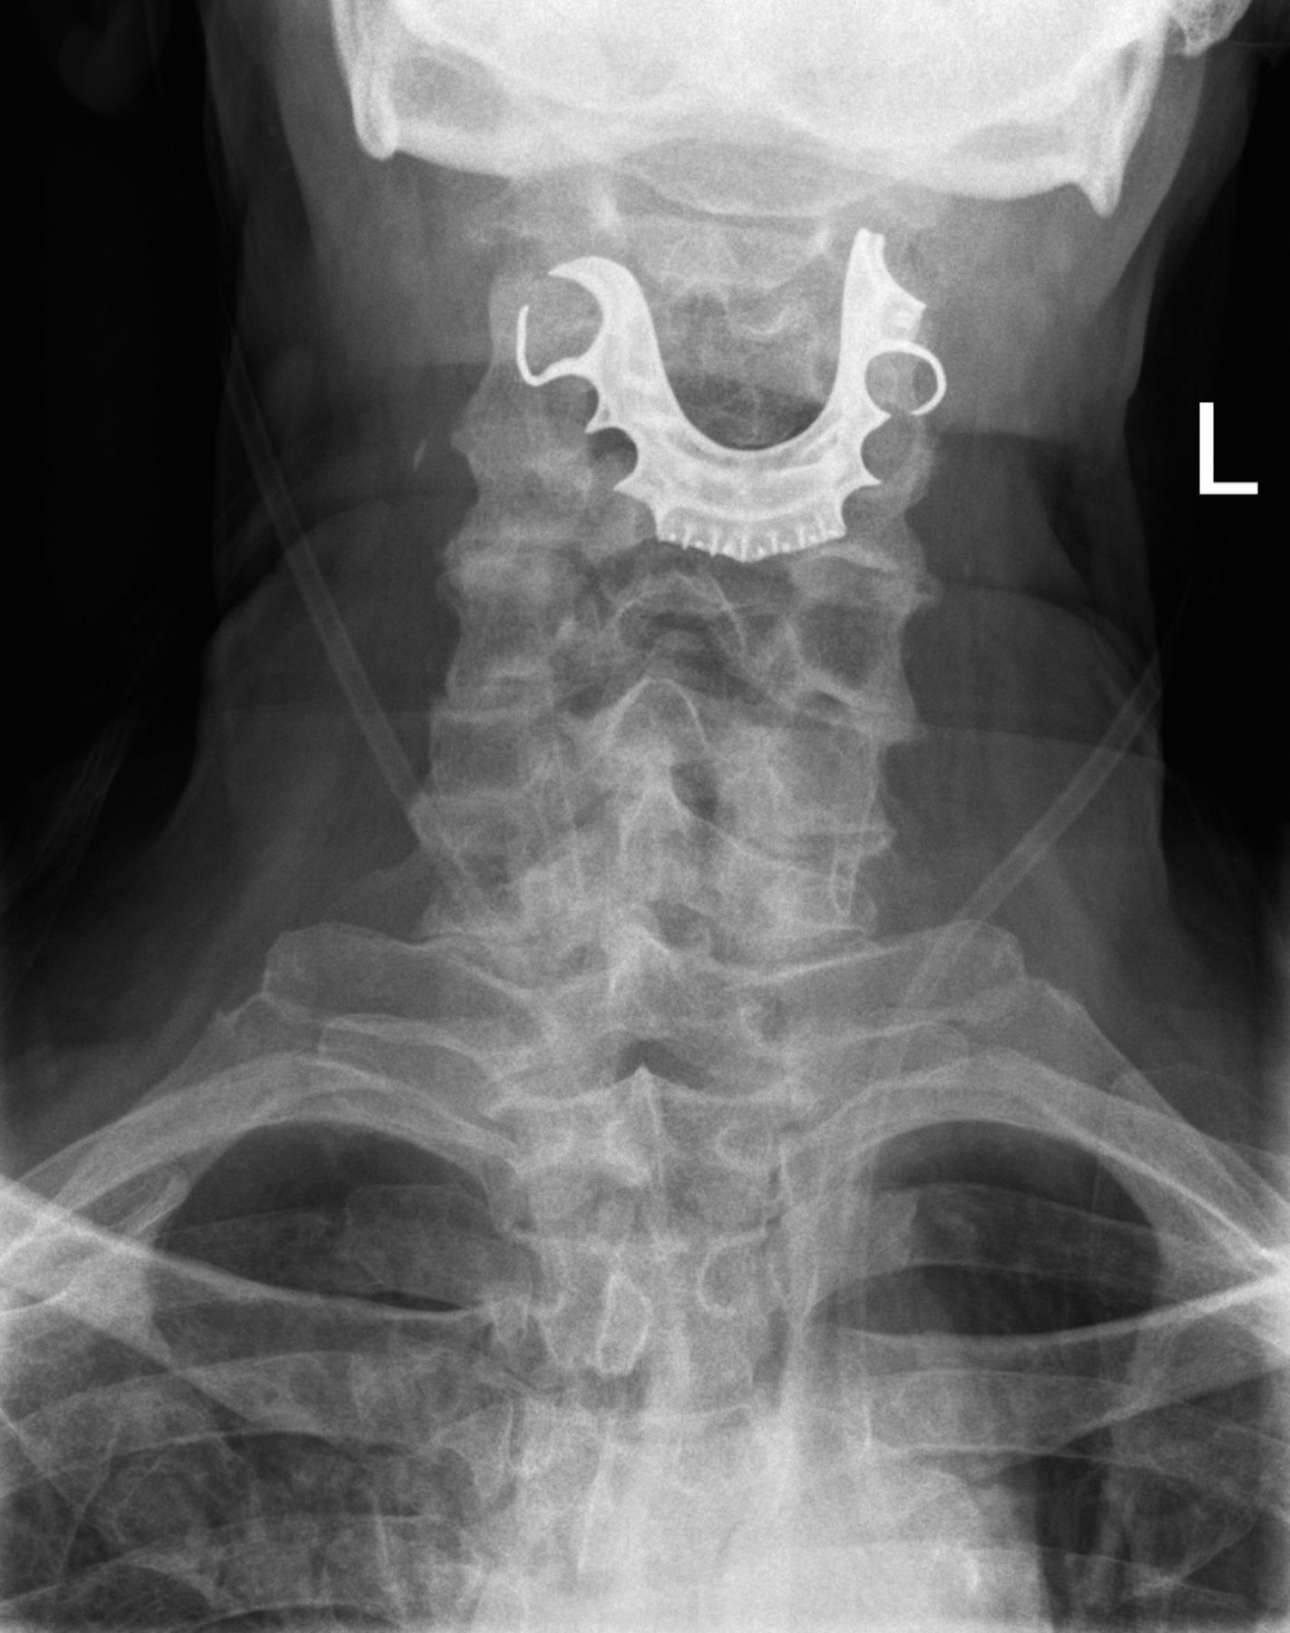

Τελικά, μέσω μιας διαγνωστικής διαδικασίας οι γιατροί εντόπισαν το ημικυκλικό αντικείμενο σφηνωμένο πάνω στις φωνητικές χορδές του, που είχε προκαλέσει φουσκάλες και πρήξιμο.

Ο 72χρονος, που είχε χάσει την μασέλα του κατά την πρώτη του επίσκεψη στο νοσοκομείο αλλά δεν είχε φανταστεί ότι αυτή βρισκόταν στον… λαιμό του, εισήχθη εσπευσμένα στο χειρουργείο για την αφαίρεσή της.